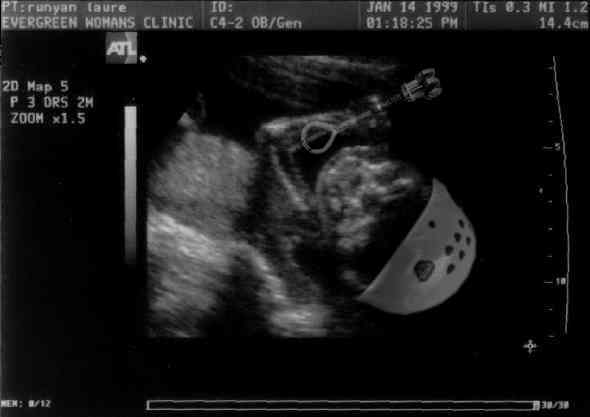

Placing Pro in Mommy's Tummy!

Baby training early for the Runyan way of life!